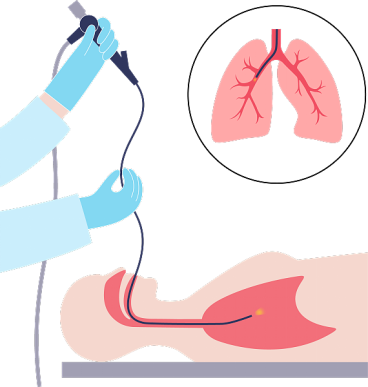

支气管镜是一种细长的、柔软的、可弯曲的管状仪器,它通过鼻腔或口腔插入,经过咽喉、气管,最终到达支气管。支气管镜上配备有光源和摄像头,能够将呼吸道内部的影像实时传输到显示屏上,让医生清晰地观察气管和支气管的管壁、管腔以及周围组织的情况。